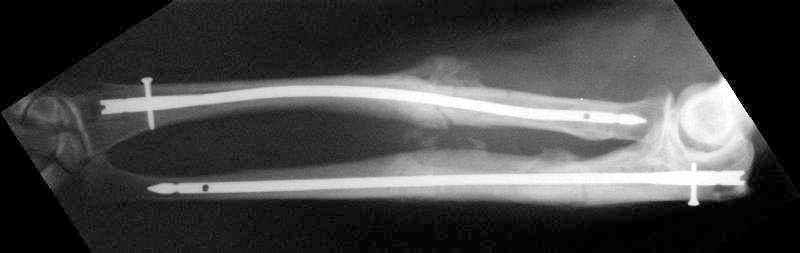

Closed nailing was performed by 4 mm stainless steel implants (ChM, Poland). I decided to lock both dynamically because of shape of bone ends which prevents rotation and telescoping. Images attached. Comments and critics are welcome.

![]() |

The reductions are nice, but I'd be concerned that the fracture of the radius will move with pronation & supination encouraging nonunion (since the nail is essentially fixed to the distal radial shaft and free to move with respect to the proximal radius.

I'd lean toward 4-5 weeks in a long arm cast, giving him "credit" for the past week or so of immobilization.

I suppose it won't because of shape of bone ends and also 3 point fixation by the bent nail.

The reduction is excellent but I am not sure that you have rotational stability of the proximal radial fragment (no proximal locking) this could rotate with pronation and supination. If you are planning to cast then ORIF with plates is superior because casting is not necessary. I would expect these fractures to heal with callus as opposed to primary bone healing seen with plated fixation. Is healing with callus in the forearm a problem? I am not sure I know. How do these rods and locking screws compare price wise with plate and screw fixation (more expensive I would expect)? How often is hardware removal required? What was your operative time? I think these are all factors to consider when comparing a new treatment method with an established one.

I tried rotation under image inensifier and all looks stable enough. Of course he won't be encouraged to perform forced rotation immediately.